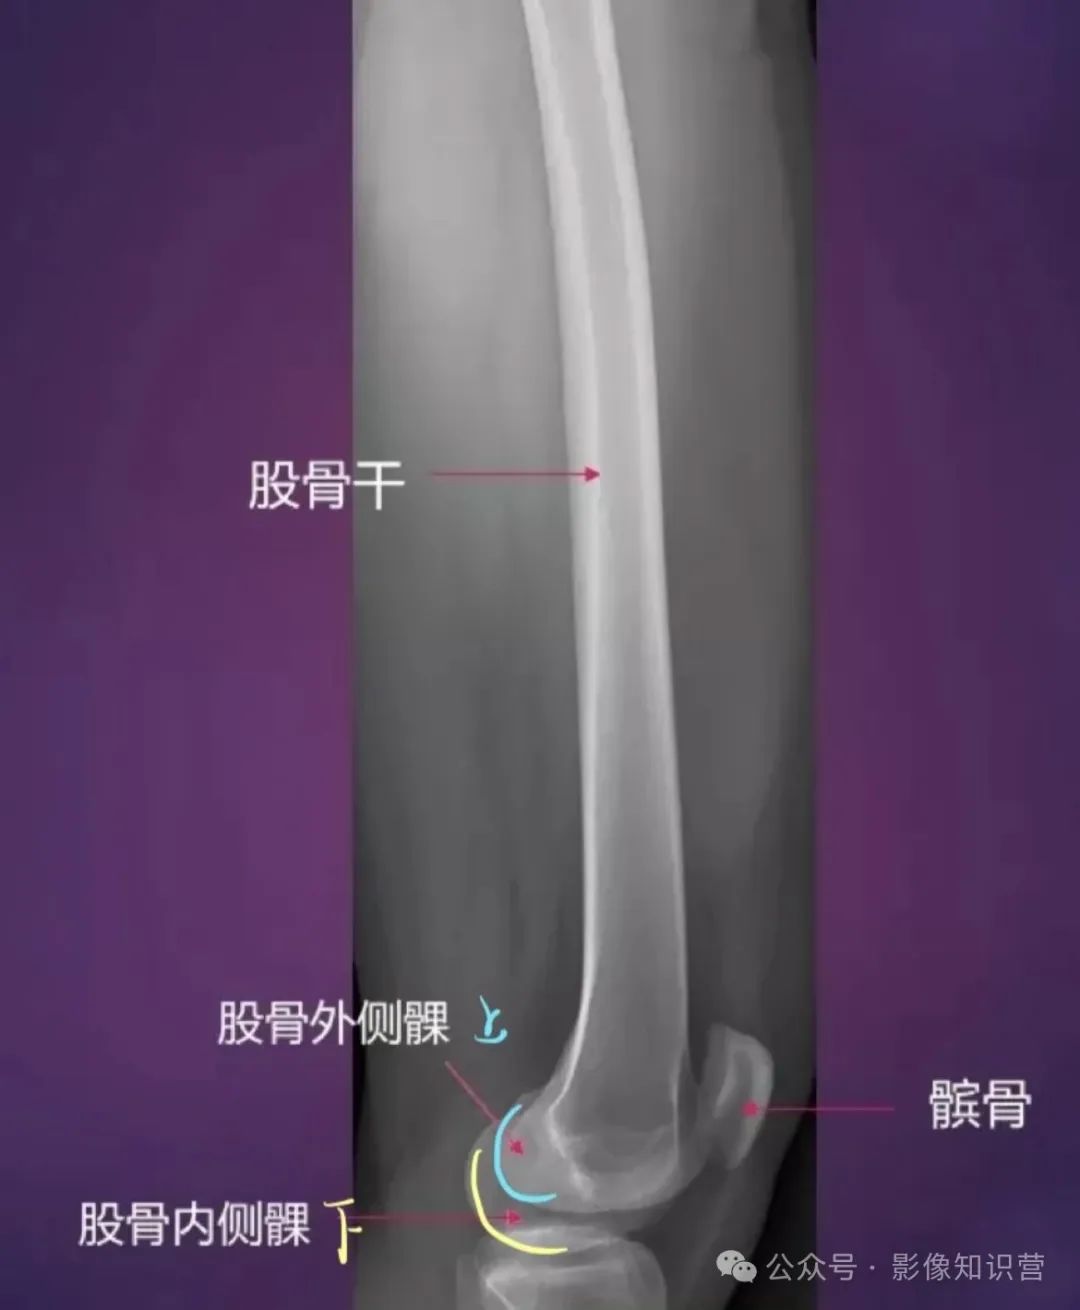

股骨:是人体最长最结实的长骨。股骨头呈球形,与髋臼构成髋关节。股骨颈与股骨干之间形成颈干角。股骨体后方有粗线,是肌肉附着处。股骨下端有内侧髁和外侧髁,与胫骨和髌骨相关节。

解剖标志:股骨头、股骨颈、大转子、小转子、股骨干、股骨髁(内、外侧髁)。

膝关节骨骼组成:股骨远端、胫骨近端、髌骨。

影像特征:X线侧位:观察髌骨位置及关节间隙(正常约3-5mm)。MRI可评估半月板(内“C”形、外“O”形)、交叉韧带及软骨损伤。